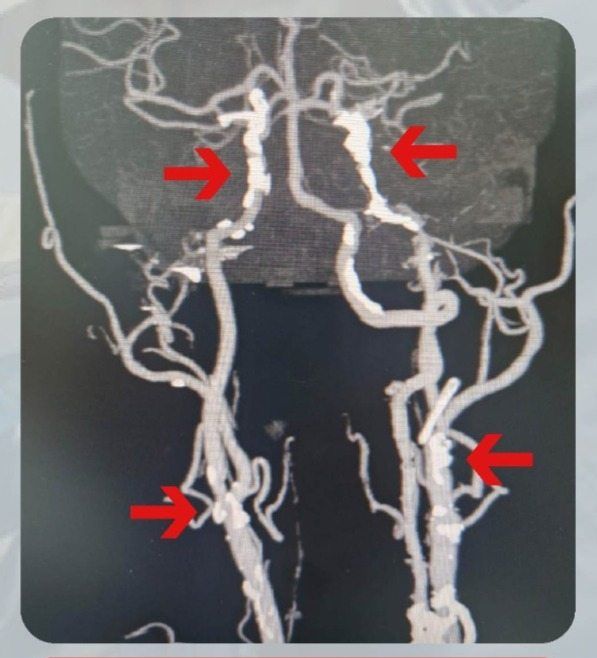

“Here I was told both my carotid arteries were blocked by 95% and 75% respectively, and I needed surgery.

According to Dr Yow, carotid stenosis from narrowing in the neck area is the fastest rising cause of ischaemic stroke in the world, particularly in the Asian region.

“The risk of a stroke is greatest when the narrowing in the neck is higher than 50% (classified as critical carotid stenosis).

So, if you experience a TIA, head to the doctor as soon as possible and request for a carotid artery ultrasound or computed tomography (CT) angiography.